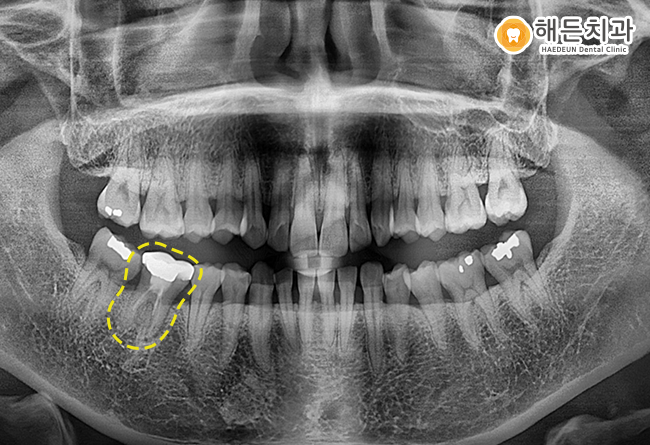

정밀한 체크를 위해, 파노라마 사진을 촬영해 확인해보니

치아 상태가 좋지 않아보였는데요.